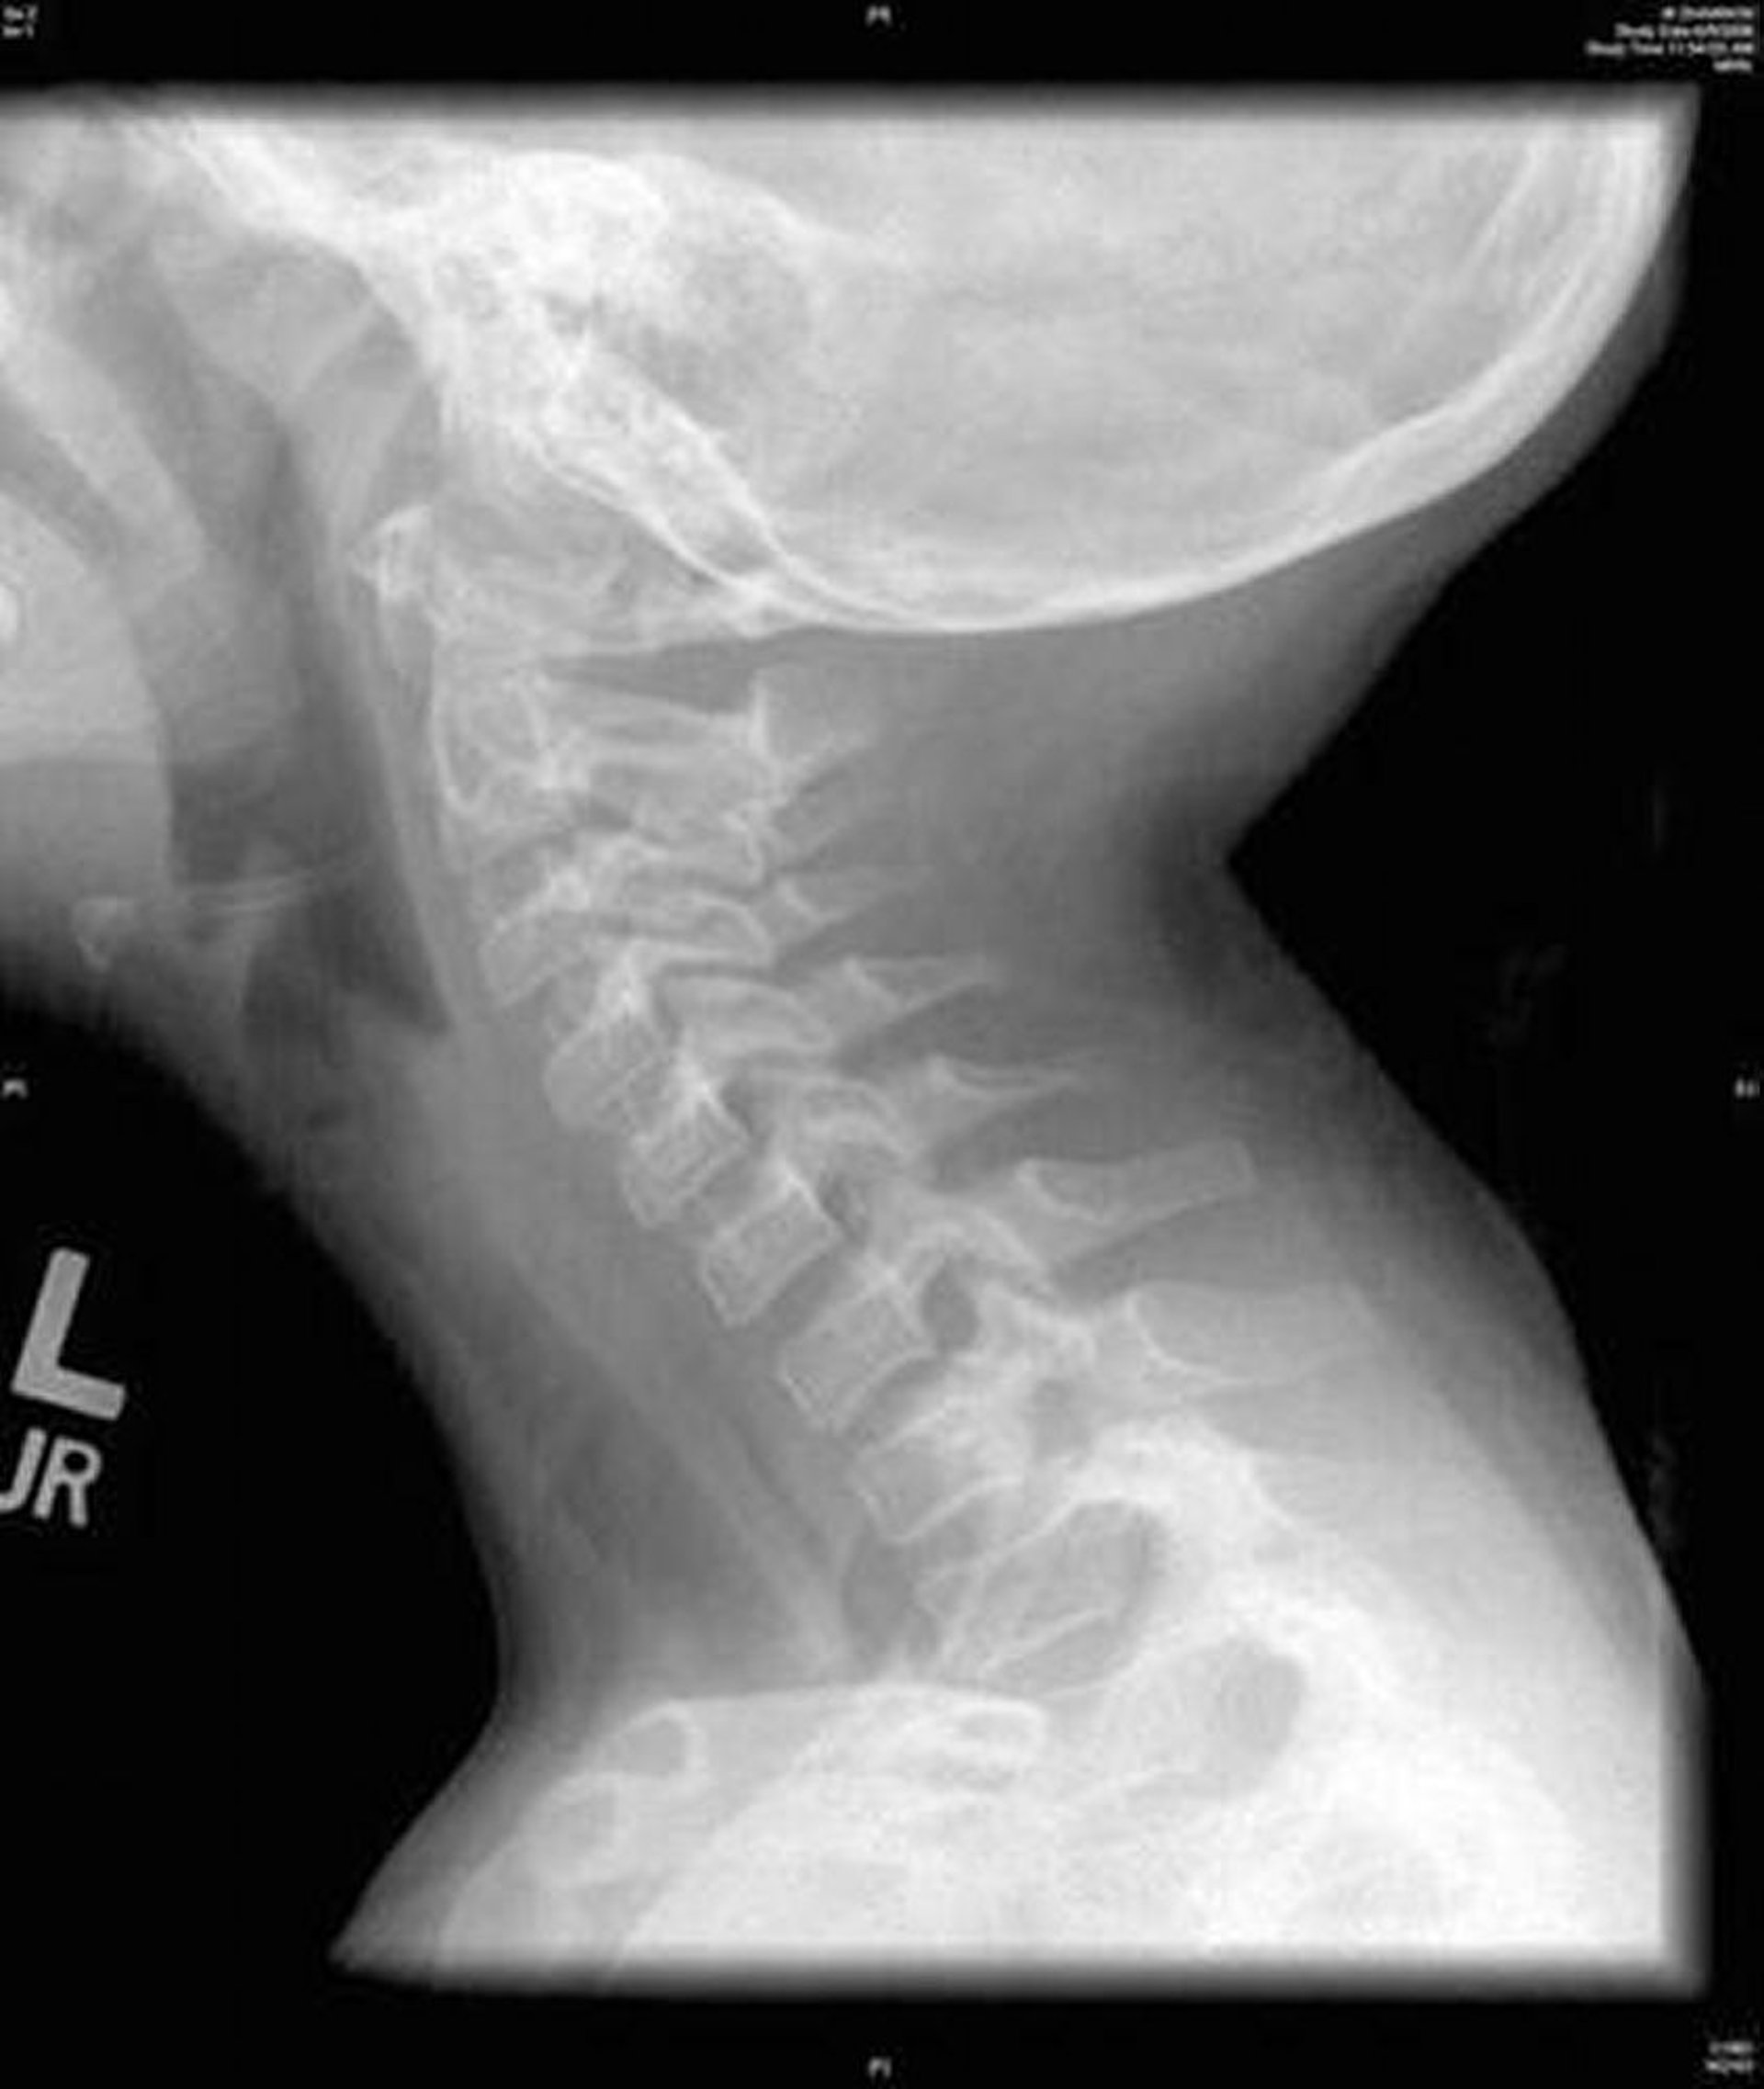

Esta imagen muestra una radiografía lateral del cuello que revela una irregularidad difusa de la tráquea característica de la traqueítis bacteriana.